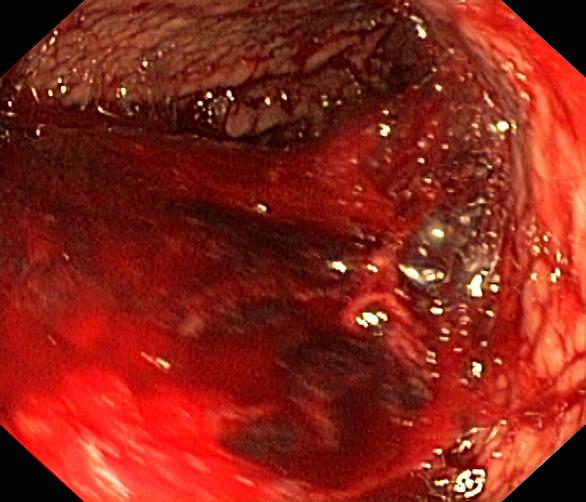

Krwawienie

Wrzód trawienny